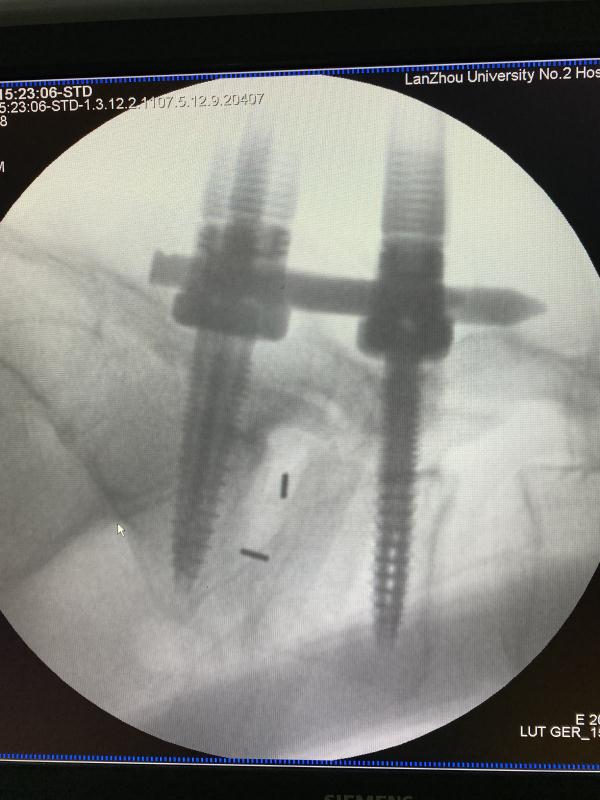

近日,兰大二院骨科二病区张海鸿主任团队开展一例显微镜辅助下Zista通道MIS-TLIF,手术由张海鸿主任指导,成鹏副主任医师和李宏伟医师共同完成。

患者,女性,47岁,左下肢疼痛伴麻木1年,加重两月。入院后,骨科医护团队立即完善相关检查,仔细察看患者病情发展情况,为其制定了精准的治疗方案,同时向患者及家属详细讲解了手术的优势及术后的注意事项,患者及家属表示理解并同意手术。术中一切顺利,术后患者次日即可下地活动,大大缩短了传统Tlif术后需卧床三月的修复时间。

MIS-TLIF较传统TLIF而言具有以下六点优势:一是对肌肉组织损伤更小。技术的入路为Wiltse多裂肌与最长肌间隙进入,明显减少肌肉损伤,经皮钉固定只需用四针线缝合即可;二是对翻修病例有优势。MIS-TLIF则恰恰避开了第一次手术造成的瘢痕粘连这些不正常的解剖入路,从侧方正常结构进行分离解剖、损伤神经的机会明显减少;三是适应症广。与其他微创融合术相比,如OLIF、DLIF等,其可以直接减压,适应症更广泛;四是神经损伤的可能性减少。无需牵拉硬膜囊或神经根,降低术后因牵拉引起的马尾神经损害的并发症;五是术中出血量少、住院时间短。(这例病人第二天即可下地活动);六是大量文献表明MIS-TLIF的手术效果能够达到与传统开放手术一样的手术效果。成鹏副主任医师也表示Zista通道较可扩张通道有明显微创优势,对椎旁肌肉损伤更小,同时有更便于调整通道位置实现精准减压。